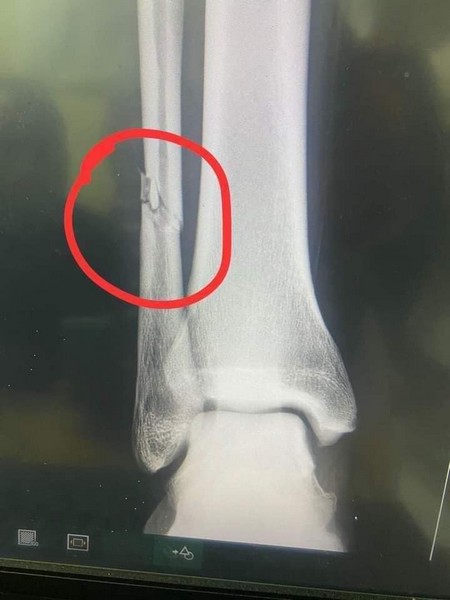

Rimsport - Après avoir subi un tacle violent d'undéfenseur de Simba Sc, dimanche (13 mars) en match comptant pour la quatrième journée de la Coupe de la Confédération - CAF, Adama Ba a révélé sur les réseaux sociaux souffrir d'une fracture du péroné de la jambe droite.

Un tacle extrêmement violent au tibia du joueur tanzanien, et Adama Ba qui crie de douleur. Les images font froid dans le dos. L'attaquant mauritanien de RS Berkane, revenu au meilleur de sa forme, après sa retraite internationale a été sévèrement blessé.

Sa période d'indisponibilité pourrait dépasser un mois. La défaite des marocains (0-1), en déplacement est forcément passée au second plan après cette grave.